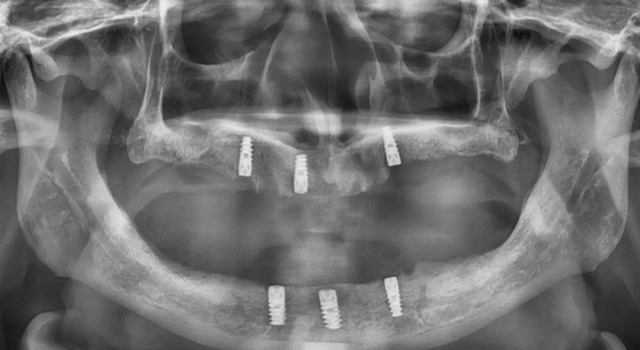

全景片显示口腔内上下各3颗种植体

“老人说自己做了全口种植,但他上下都只种了3颗种植体,与全口种植上下各种4-6颗种植体并不相符,全口种植后通常会安装临时的固定牙冠,方便过渡时期使用,而他安装的却是活动假牙。”